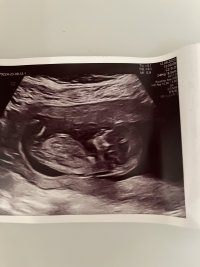

Tatt i uke 12. Noen tanker om kjønn?